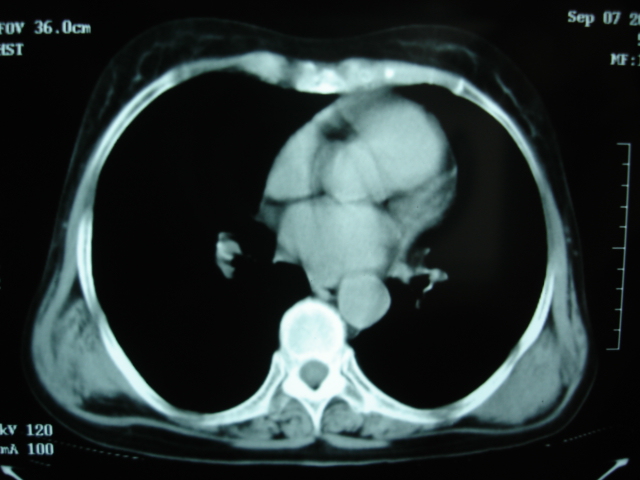

以下是引用卜一在2009-9-7 19:51:00的发言:[br][br] 1 左侧胸内甲状腺占位-多考虑甲状腺腺瘤! 2、左肺门占位-建议增强扫描以便明确性质。 3 慢支并感染! [br]

以下是引用shibing在2009-9-7 20:40:00的发言:[br]左侧胸内甲状腺占位-多考虑甲状腺腺瘤! 2、左肺门占位-建议增强扫描以便明确性质。 3 慢支并感染! [br]